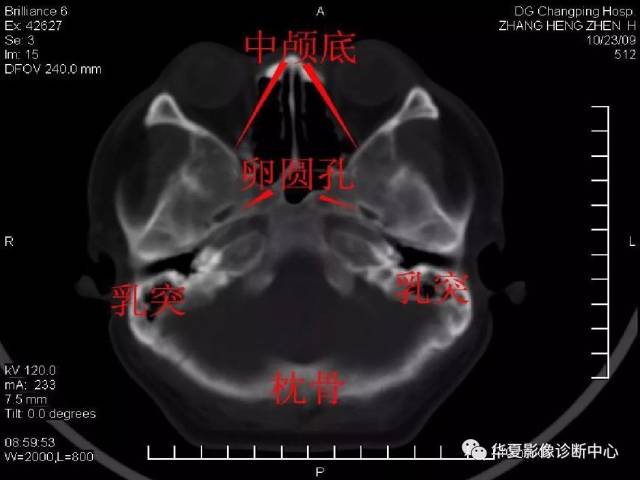

颅底ct高清图解 常见骨折部位图示

颅底ct

颅底解剖图ct

颅底ct断层解剖骨窗

颅底骨断层解剖图ct